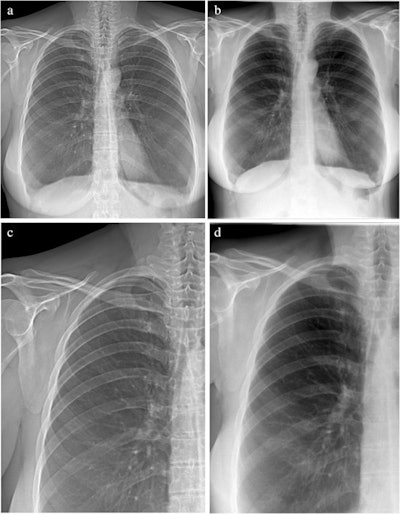

Attenuation images of a 42-year-old woman with COPD (GOLD III). (A) Attenuation image acquired with the prototype. (B) Attenuation image acquired at the commercial system. Images C and D show enlarged extracts from A and B, respectively. Image courtesy of European Radiology through CC BY 4.0.Five radiologists independently assessed the visibility of anatomical structures, the level of motion artifacts, and the overall image quality of all attenuation images on a five-point scale, with five points being the highest rating.

Overall image quality was rated high for both devices, 4.2 for the prototype and 4.6 for the commercial system, according to the results. The rating scores varied only slightly between both image types, especially for structures relevant to lung assessment, where the images from the commercial system were graded slightly higher, the authors wrote.

In addition, for the assessment of motion artifacts, the images from the commercial system achieved a mean rating of 4.9, whereas the grating-based images from the prototype scored 4.1 on average.